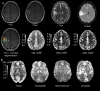

Background: Evaluation of molecular markers (IDH, pTERT, 1p/19q codeletion, and MGMT) in adult diffuse gliomas is crucial for accurate diagnosis and optimal treatment planning. Dynamic Susceptibility Contrast (DSC) and Arterial Spin Labeling (ASL) perfusion MRI techniques have both shown good performance in classifying molecular markers, however, their performance has not been compared side-by-side.

Methods: Pretreatment MRI data from 90 patients diagnosed with diffuse glioma (54 men/36 female, 53.1 ± 15.5 years, grades 2-4) were retrospectively analyzed. DSC-derived normalized cerebral blood flow/volume (nCBF/nCBV) and ASL-derived nCBF in tumor and perifocal edema were analyzed in patients with available IDH-mutation (n = 67), pTERT-mutation (n = 39), 1p/19q codeletion (n = 33), and MGMT promoter methylation (n = 31) status. Cross-validated uni- and multivariate logistic regression models assessed perfusion parameters' performance in molecular marker detection.

Results: ASL and DSC perfusion parameters in tumor and edema distinguished IDH-wildtype (wt) and pTERT-wt tumors from mutated ones. Univariate classification performance was comparable for ASL-nCBF and DSC-nCBV in IDH (maximum AUROCC 0.82 and 0.83, respectively) and pTERT (maximum AUROCC 0.70 and 0.81, respectively) status differentiation. The multivariate approach improved IDH (DSC-nCBV AUROCC 0.89) and pTERT (ASL-nCBF AUROCC 0.8 and DSC-nCBV AUROCC 0.86) classification. However, ASL and DSC parameters could not differentiate 1p/19q codeletion or MGMT promoter methylation status. Positive correlations were found between ASL-nCBF and DSC-nCBV/-nCBF in tumor and edema.

Conclusions: ASL is a viable gadolinium-free replacement for DSC for molecular characterization of adult diffuse gliomas.